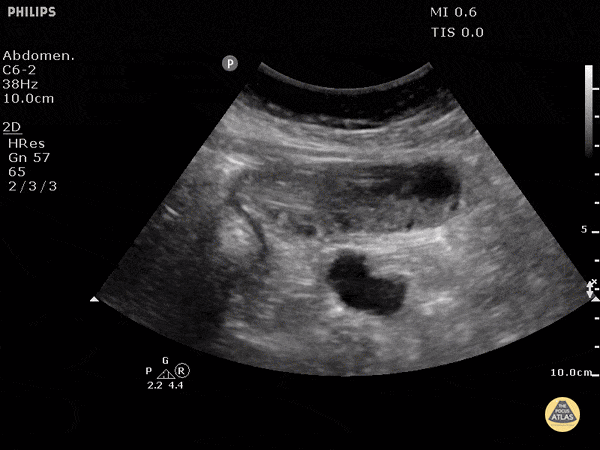

Bowel-GI - Small Bowel Obstruction

This image demonstrates a dilated loop of small bowel with to and fro movements of stool contents. POCUS has been shown to have a sensitivity of 0.91 and specificity of 0.84 for this indication in a single trial when EM residents performed the study. This is compared to 0.02 and 0.67 for an old fashioned KUB. Jang TB, et al. Bedside ultrasonography for the detection of small bowel obstruction in the emergency department. J Emerg Med. 2011. 28(8):676-678. Submitted by Dr. Justin Bowra et al.